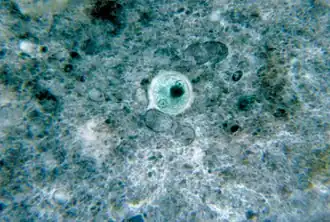

L'examen direct au microscope optique sur plaque chauffante est longtemps restée la méthode de diagnostic la plus répandue dans le monde entier. Cet examen permet de voir les formes végétatives minuta et histolytica en mouvement (sous l'influence de la chaleur), et affirmer E. histolytica avec certitude lors de la mise en évidence de trophozoïtes hématophages[23].

Les kystes sont identifiés par des techniques de concentration[27], mais ils ne sont pas constamment présents et l'analyse de plusieurs prélèvements successifs est parfois nécessaire. Cet examen permet de distinguer les kystes des amibes non pathogènes, tels que celui d'Entamoeba coli qui possède jusqu'à 8 noyaux, décentrés à contours irréguliers.

Cependant, l'examen optique ne permet pas le diagnostic différentiel avec Entamoeba dispar beaucoup plus répandu, d'où l'appellation d'un complexe Entamoeba histolytica/dispar. L'OMS recommande de ne pas traiter les infections diagnostiquées par le seul examen au microscope si elles sont asymptomatiques.

Quand les examens parasitologiques sont négatifs, le sérodiagnostic et la rectoscopie sont des examens d'appoints. Le sérodiagnostic est négatif dans les dysenteries aigües, mais il tend à devenir positif par la suite.

La rectoscopie montre une muqueuse inflammatoire et hémorragique avec des ulcérations « en coup d'ongle ». La biopsie colique peut montrer en phase aigüe les microabcès « en bouton de chemise », et en cas d'amœbome, un granulome inflammatoire.